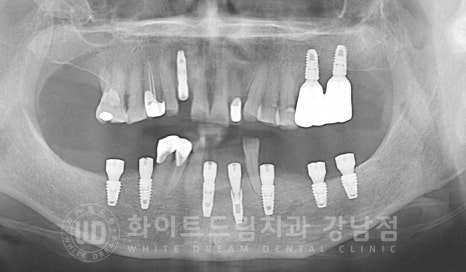

발치 & 뼈이식 임플란트 동시 진행 (수술일자 : 23.08.19)

뼈이식을 동반했기에 4개월의 회복 기간을 가지면서

이식재가 새로운 뼈로 형성되고, 식립된 임플란트는 새로운 뼈와 잘 유착될 수 있도록

지켜보는 시간을 가지게 됩니다.

총 치료 기간 : 23.08.18 - 24.01.16

초기 잇몸뼈 흡수가 심했던 부분들도 잇몸뼈가 잘 형성되었고

함께 식립한 임플란트도 이상 없이 제 기능을 발휘하고 있습니다.